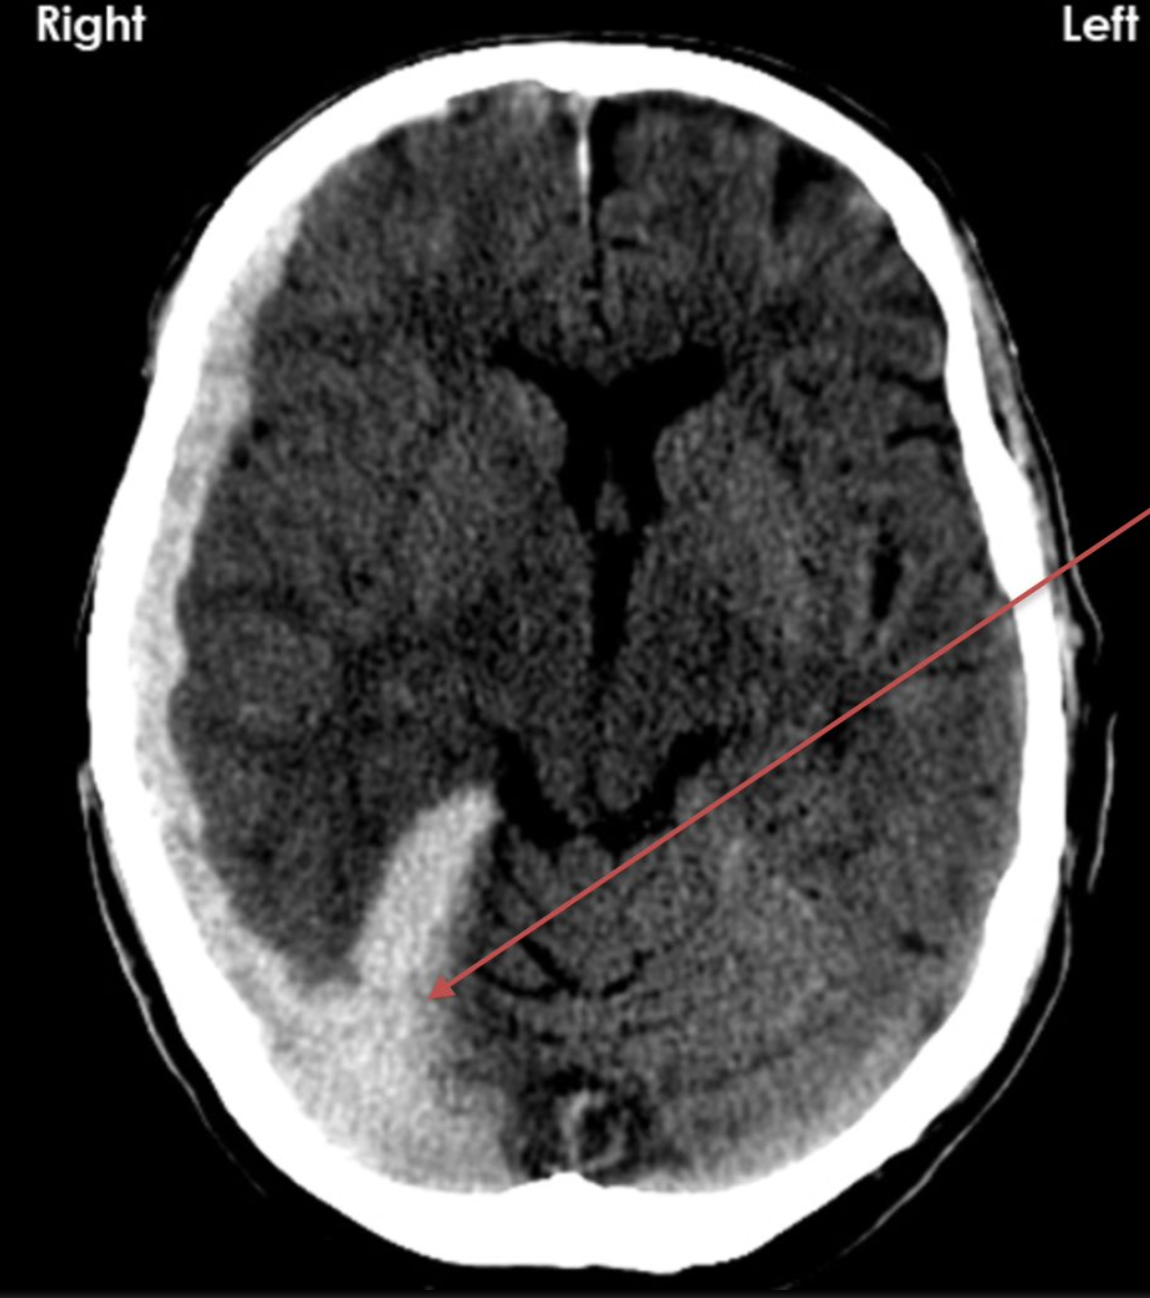

epidural haematoma

subdural haematoma

infarct